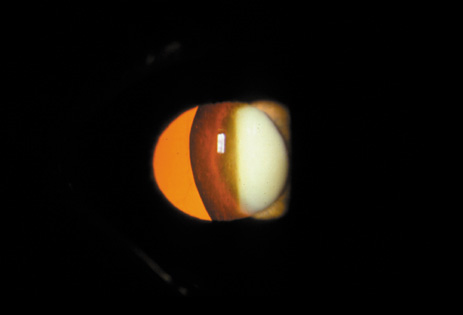

The PSC is the least prevalent subtype in most population-based studies.18 These cataracts often occur in combination with nuclear or cortical cataracts in the later stages. They are easily noticed on retroillumination because they are usually located centrally, and may interfere with funduscopy (Fig. 12). In early stages, patients usually complain of subjective symptoms such as glare disability32 and difficulty focusing on near objects. This is because when the pupil constricts during accommodation, the light entering the eye becomes concentrated centrally, where the PSC is also located. This causes light scattering and interferes with the ability of the eye to focus an image on the macula. In addition, these opacities lie at or near the nodal point of the eye, further interfering with focusing of the image on the macula.

Fig. 12. PSC. Note the central location, which gives rise to severe glare disability.